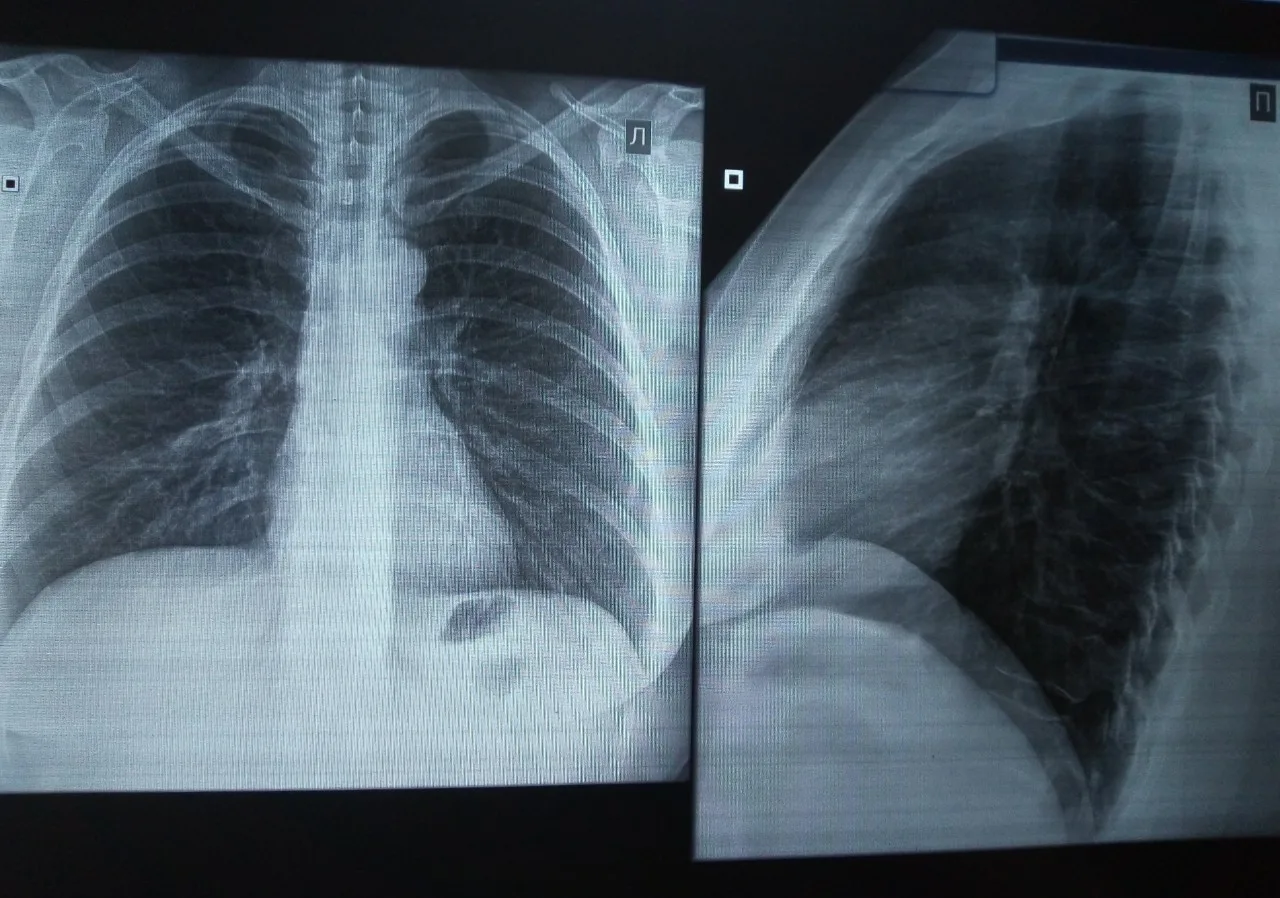

Рентген легких – это один из наиболее распространенных и доступных методов диагностики, позволяющий оценить состояние легких и выявить различные заболевания органов грудной клетки. Этот метод основан на использовании рентгеновских лучей, которые проникают через ткани тела и создают изображение на специальной пленке или цифровом детекторе. Рентген легких позволяет врачам увидеть изменения в легких, сердце, кровеносных сосудах и костях грудной клетки, что помогает в постановке диагноза и назначении эффективного лечения.

Рентген легких позволяет выявить широкий спектр заболеваний и состояний, включая:

- Пневмонию: Воспаление легких, вызванное бактериальной или вирусной инфекцией. На рентгеновском снимке пневмония выглядит как затемнение в легких.

- Туберкулез: Инфекционное заболевание, поражающее легкие. На рентгеновском снимке туберкулез может проявляться в виде очагов, полостей или рубцов.

- Рак легких: Злокачественная опухоль в легких. На рентгеновском снимке рак легких может выглядеть как узел, затемнение или увеличение лимфатических узлов.

- Плеврит: Воспаление плевры (оболочки, окружающей легкие). На рентгеновском снимке плеврит может проявляться в виде жидкости в плевральной полости.

Процедура рентгена легких обычно занимает несколько минут и проводится в рентгеновском кабинете. Пациент раздевается до пояса (или до нижнего белья) и становится перед рентгеновским аппаратом. Медицинский работник просит пациента сделать глубокий вдох и задержать дыхание на несколько секунд, в течение которых делается снимок. В некоторых случаях может потребоваться сделать несколько снимков в разных проекциях.